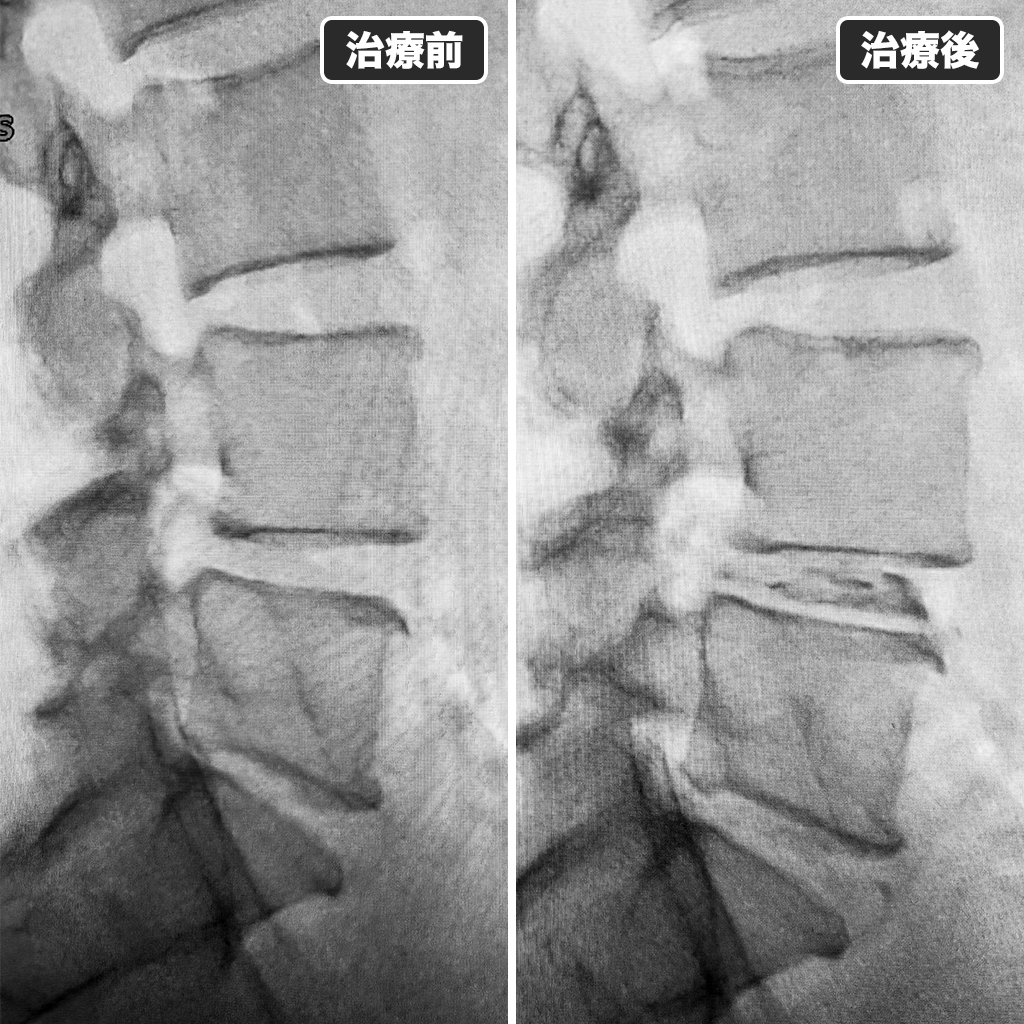

治療前後のレントゲン

治療前後のレントゲン写真です。左側が治療前、右側が治療後です。